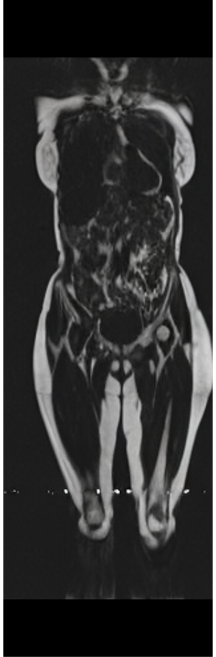

In this work, we present X-Diffusion, a cross-sectional diffusion model tailored for Magnetic Resonance Imaging (MRI) data. X-Diffusion is capable of generating the entire MRI volume from just a single MRI slice or optionally from few multiple slices, setting new benchmarks in the precision of synthesized MRIs from extremely sparse observations. The uniqueness lies in the novel view-conditional training and inference of X-Diffusion on MRI volumes, allowing for generalized MRI learning. Our evaluations span both brain tumour MRIs from the BRATS dataset and full-body MRIs from the UK Biobank dataset. Utilizing the paired pre-registered Dual-energy X-ray Absorptiometry (DXA) and MRI modalities in the UK Biobank dataset, X-Diffusion is able to generate detailed 3D MRI volume from a single full-body DXA. Remarkably, the resultant MRIs not only stand out in precision on unseen examples (surpassing state-of-the-art results by large margins) but also flawlessly retain essential features of the original MRI, including tumour profiles, spine curvature, brain volume, and beyond. Furthermore, the trained X-Diffusion model on the MRI datasets attains a generalization capacity out-of-domain (e.g. generating knee MRIs even though it is trained on brains). The code is available on the project website https://emmanuelleb985.github.io/XDiffusion/.

Recently, the use of diffusion-based models for image inverse problems has shown great success [63, 18, 35, 51, 40, 52]. This motivated our X-Diffusion to investigate learning volumes instead of images. In this light, our X-Diffusion proposes a novel architecture to allow learning on 3D volumetric data by view-dependent cross-sections. This allows for full MRI generation with unprecedented accuracy from a single MRI slice, multiple slices, or even from DXA image if paired data is available (see Figure 1). To the best of our knowledge, X-Diffusion is the first work to successfully generate detailed MRI volumes from a single DXA scan, bridging the gap between two common data modalities in medical imaging. It is important to note that the generated MRIs are not clinical replacements for true MRIs, but could provide a quick, affordable, and informative “pseudo-MRI" before conducting a full MRI examination.

Contributions: (i) We introduce X-Diffusion, a cross-sectional diffusion model that generates MRI slices conditioned on a single input MRI slice or multiple slices. The proposed X-Diffusion achieves state-of-the-art results on MRI reconstruction and super-resolution compared to recent methods on BRATS, a large public dataset of annotated MRIs for brain tumours. (ii) We adapt our X-Diffusion to leverage paired and registered full-body MRI and DXA images from UK Biobank dataset to generate full-body 3D MRI from a single DXA for the first time in the literature. (iii) We validate the generated MRIs on a wide range of tasks that ensure the generated MRIs retain important features of the original MRIs, including tumor profiles, spine curvature, brain volume, and more, without using this meta-information in the generation process. (iv) We showcase the generalization of trained X-Diffusion on different datasets (knee MRIs) illustrating the potential of X-Diffusion to be the first 3D volumetric foundation model in medical imaging.

UK Biobank. A more comprehensive dataset of 48,384 full-body MRIs from more than 500,000 volunteers[67], capturing diverse physiological attributes across a broad demographic spectrum. These Dixon MRIs do not come stitched, the scans are scanned axially and there is a disparity in the bias field effect (a common artifact of MRI machines) which is strongest at the knee region. The same knee pattern is present on all samples in the dataset. UK Biobank MRIs are resampled to be isotropic and cropped to a consistent resolution (501 160 224). 48,384 whole-body MRIs are paired with antero-posterior (AP) DXA scans of the same subjects.

Notably, X-Diffusion achieves state-of-the-art dB for a few input slices while baselines require more than 60 input slices to achieve similar performance (Figure 7). The margin is more than 12 dB PSNR for the 1-slice input in both the BRATS and the UK Biobank benchmarks (see Table 1 and Figure 6). For reference, two randomly sampled MRIs from UK Biobank would have a PSNR of 15.95 dB 0.36 (on 4800 randomly sampled examples). Omitting the preprocessing step of alignment DXA to MRI, leads to a drop of PSNR on average by 2.87 dB (29.01 dB 26.14 dB). The slices from 3D reconstructed volumes at varying depths and axis of rotation, visually match the ground truths for both brain and whole-body scans (see Figures 4 and 5 left). We also plot the error map (Figure 3) and the spread of the error (Figure 5 right) of such X-Diffusion generations to highlight the differences with the ground truth MRIs.